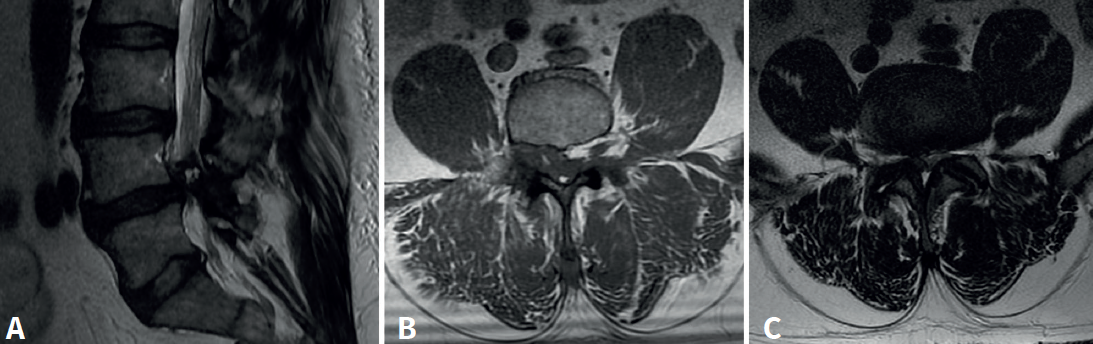

Se trata de un varón de 57 años, empleado en recogida de basura. Diez días antes de la consulta sufre una caída accidental con dolor intenso en el miembro inferior izquierdo, hipoestesia en calcetín y debilidad para la flexión y extensión del tobillo. En la exploración física presentaba Lasègue izquierdo negativo, derecho positivo a 50° y femoral stretch test derecho positivo. Se constató fuerza 1/5 en el tobillo izquierdo. La resonancia magnética (Figura 1) mostró discopatía L4-L5 con hernia discal posteromedial derecha. La electromiografía (EMG) evidenció afectación radiculoplexular izquierda moderada L3-L4 y grave L5-S1 posganglionar.